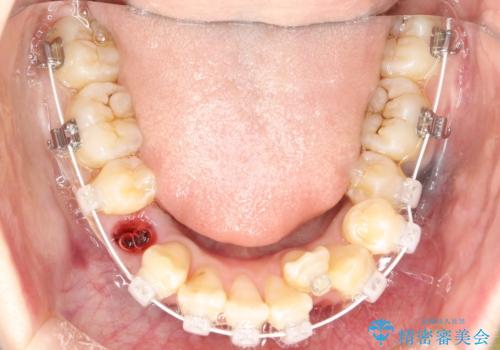

審美装置を用いた、抜歯矯正を行うこととしました。

抜歯したスペースを使うことで、ガタガタと出っ歯を改善することができました。

- 症状により、抜歯が必要な場合があります